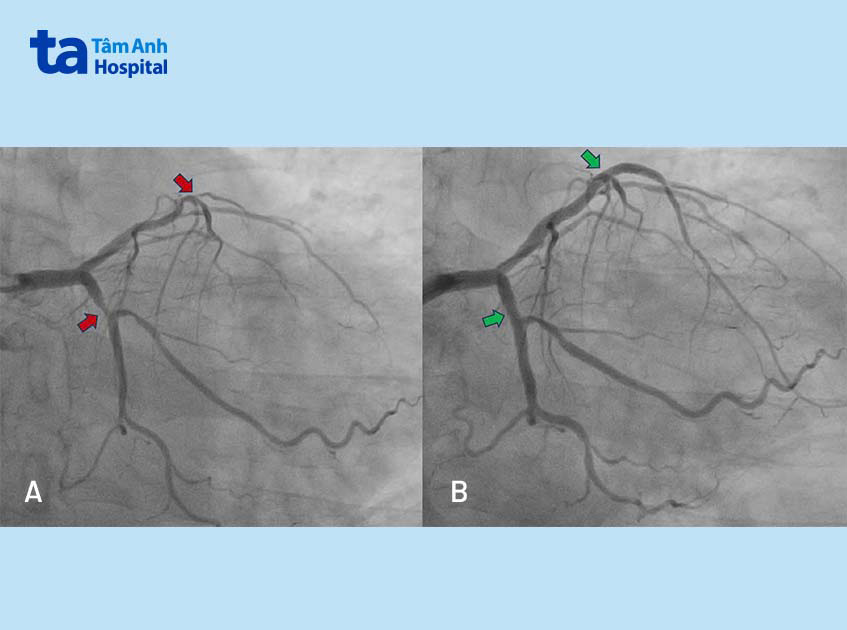

Ông Phát được chỉ định chụp mạch vành, kết quả ghi nhận ông mắc bệnh ba nhánh mạch vành biến chứng suy tim (chức năng tim EF = 25%). Đây là tình trạng ba mạch máu chính nuôi tim hẹp nặng (90-95%), cản trở phần lớn lưu lượng máu đến tim và gây thiếu máu cơ tim trầm trọng.

Bệnh nhân có biểu hiện suy tim cách đây một năm, nghĩa là bệnh đã xuất hiện trước đó nhưng không được phát hiện và điều trị kịp thời, may mắn chưa gây biến chứng nguy hiểm. Ông Phát được chỉ định can thiệp tái thông ba động mạch vành để ngăn ngừa nhồi máu cơ tim đồng thời giúp cải thiện tình trạng suy tim.

Ở ca can thiệp đầu tiên, bác sĩ luồn dây dẫn siêu nhỏ (đường kính 0.2 mm) vào đoạn giữa liên thất trước bị hẹp khít, bơm thuốc giãn mạch để lòng mạch mở rộng tối đa. Hệ thống siêu âm trong lòng mạch – IVUS giúp bác sĩ xác định vị trí đoạn mạch lành lặn nhất để bung stent, nhờ đó tránh được tình trạng xé rách mạch máu gây suy tim, ngưng tim… nếu stent bung ngay vị trí bị tổn thương.

Sau 45 phút, bác sĩ đặt được hai stent phủ thuốc vào nhánh động mạch liên thất trước. Lưu lượng máu đến tim được cải thiện đáng kể, giúp bệnh nhân hết đau ngực ngay sau can thiệp và xuất viện sau một ngày.

Một tuần sau, chức năng tim của bệnh nhân cải thiện lên mức 35%, êkíp tiến hành thủ thuật lần hai, đặt tiếp 2 stent mở rộng nhánh mạch vành phải và động mạch mũ, khơi thông toàn bộ ba con đường huyết mạch đưa máu đến tim. Bệnh nhân khỏe mạnh xuất viện vào hôm sau.